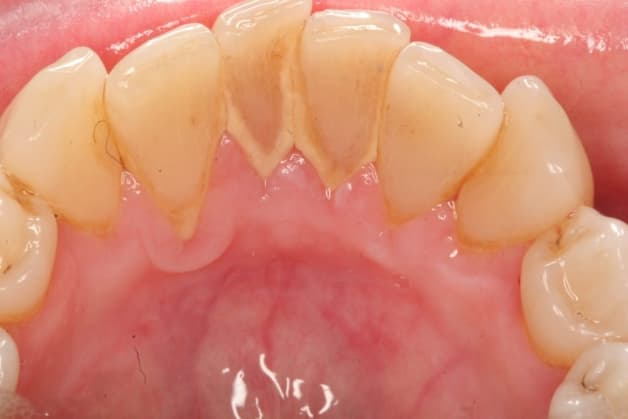

Vôi răng cấp độ 3 rất dễ phát hiện bằng mắt thường. Ở cấp độ này, cao răng đã dày, xỉn màu nghiêm trọng. Màu sắc đã chuyển sang vàng tới vàng sậm và bám nhiều trên bề mặt của răng.

Cao răng thông thường sẽ xuất hiện ở trên bề mặt phía trong của răng. Thế nhưng trong một số trường hợp ở giai đoạn này, cao răng có thể xuất hiện ngay ở mặt ngoài của răng.

Cấp độ 4 là giai đoạn cao răng nặng nhất. Khi đó, vôi răng đã chuyển từ màu vàng sẫm sang đen. Nếu như nhìn vào những người bị cao răng độ 4, ta sẽ thấy những mảng tối màu ở trên răng. Nhiều trường hợp bị nặng hơn, cao răng có thể lan xuống tới nướu và gây tình trạng cao răng dưới nướu.